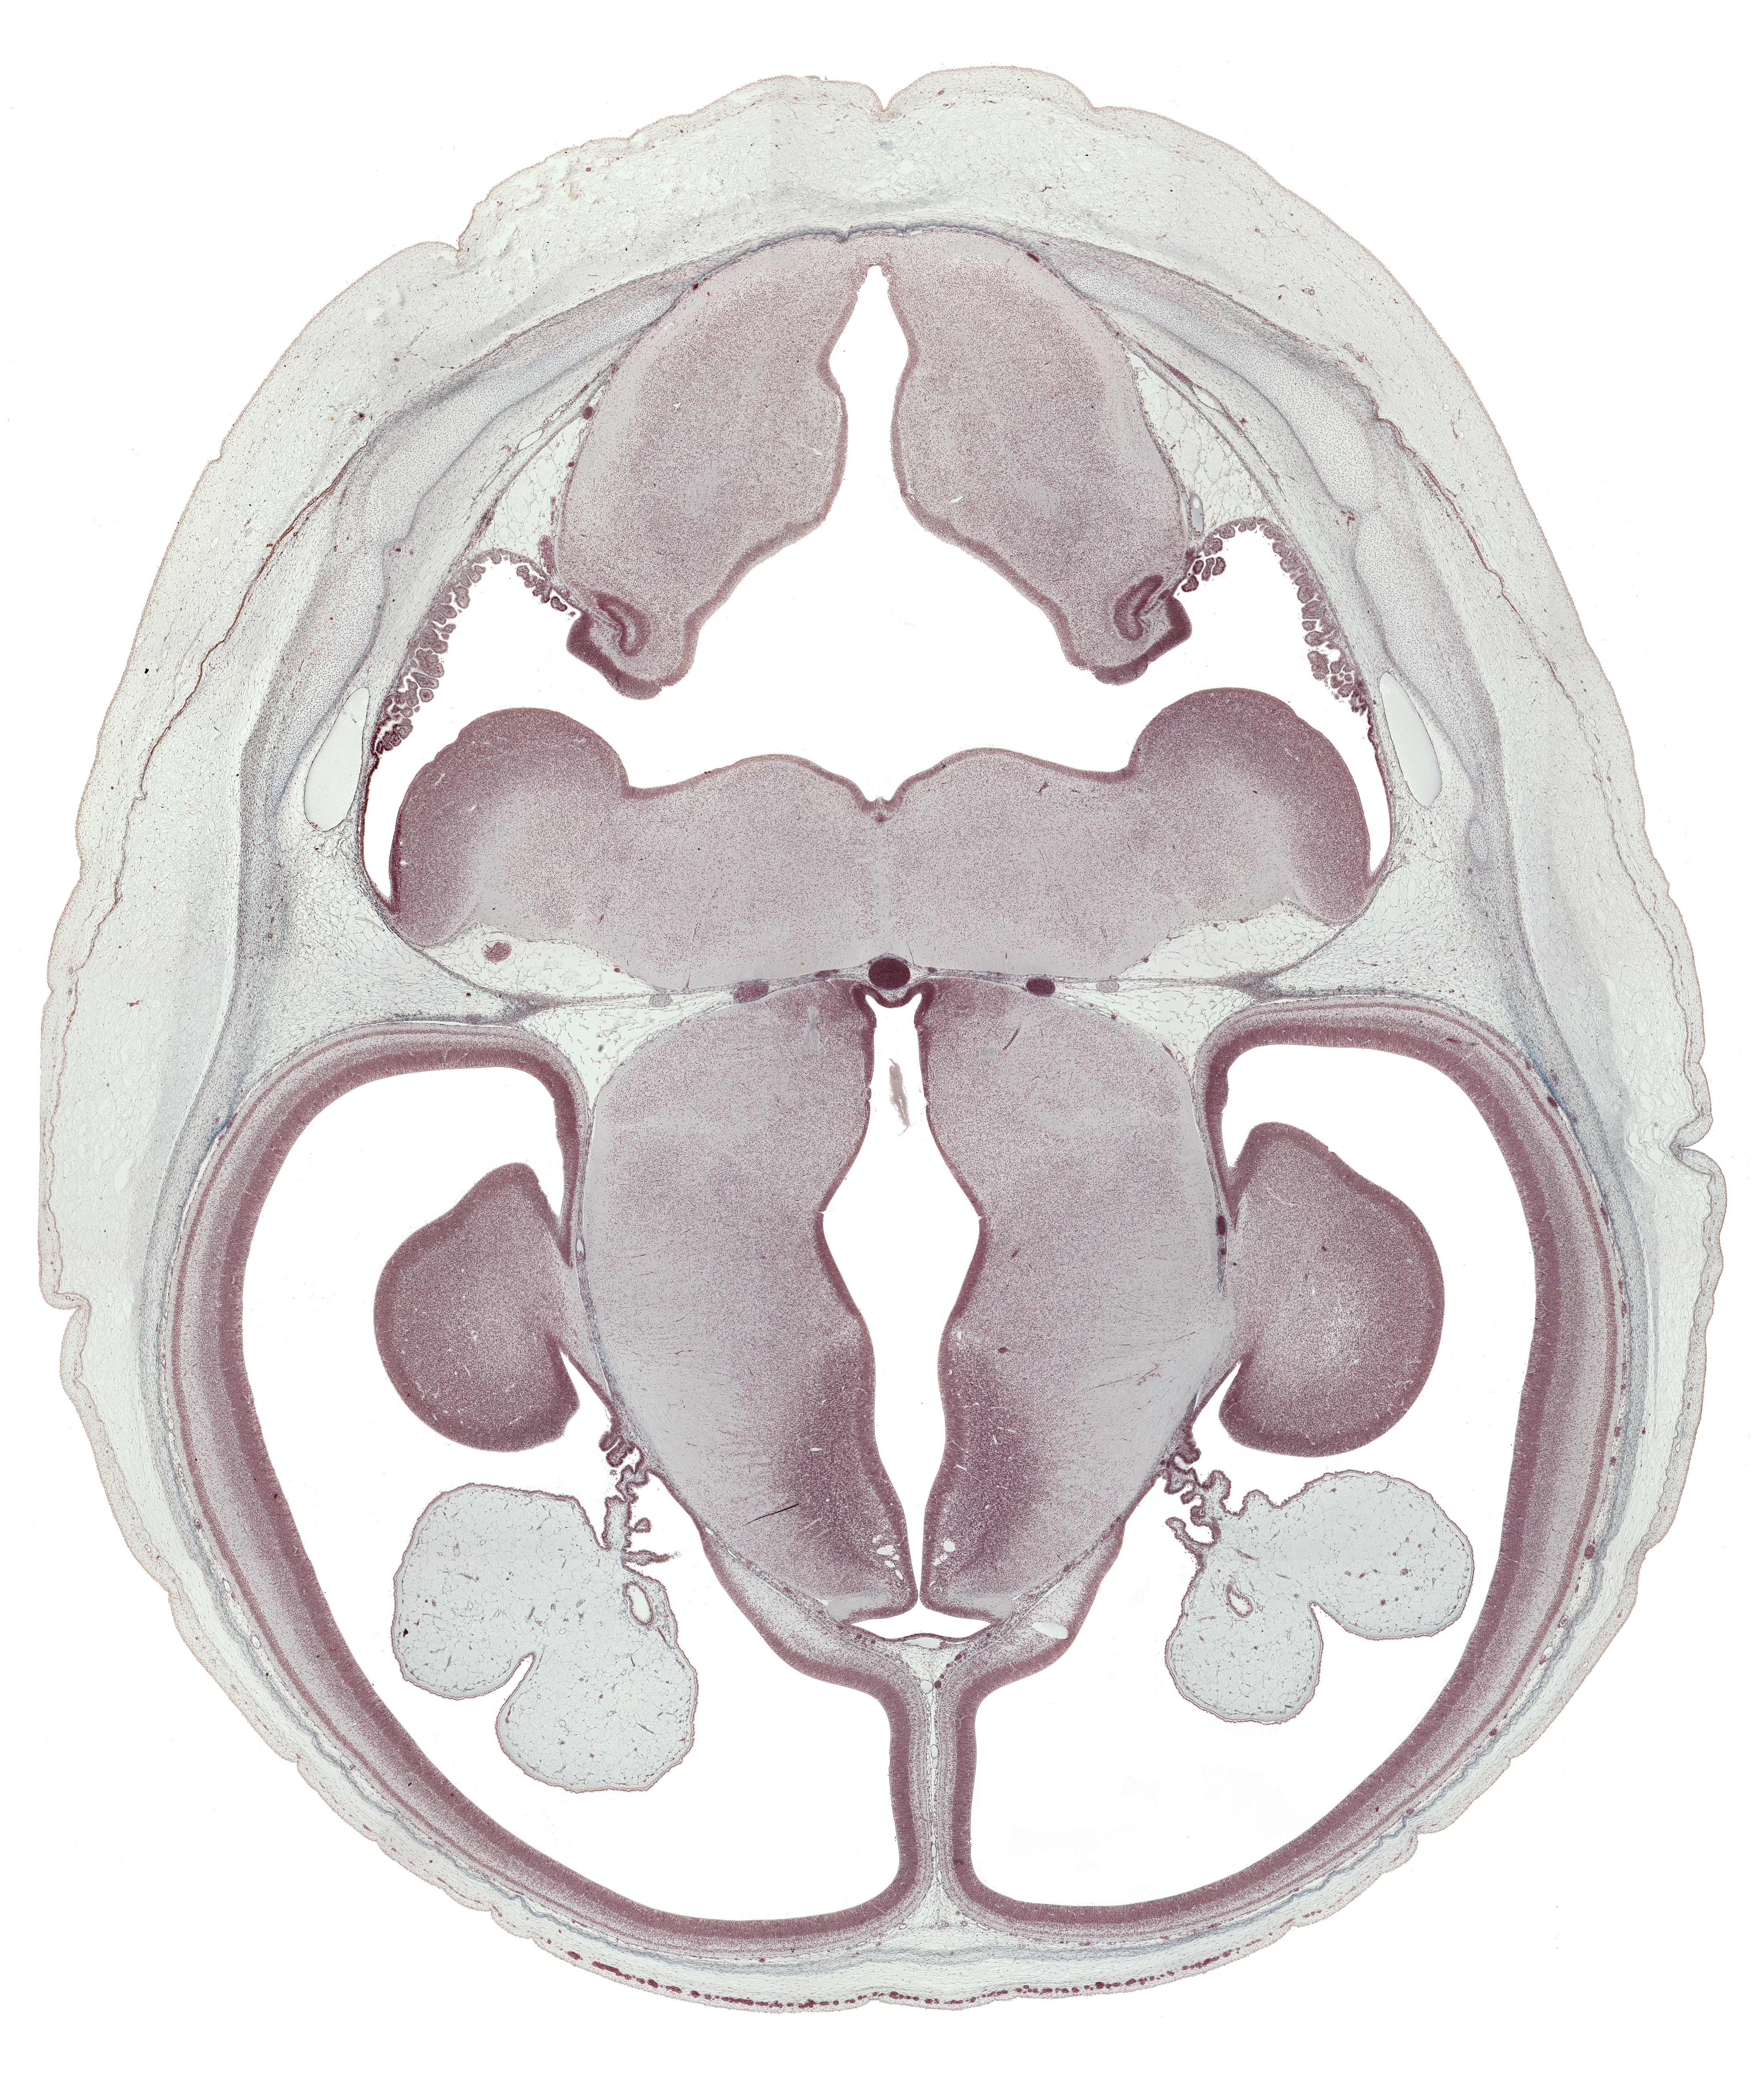

Carnegie Embryo #9226 | Location: 40-01-01

Keywords: alar plate(s), basal plate, basis pedunculi of pons region (metencephalon), external cerebellum, falx cerebri region, fusion region with anterior choroidal artery, hypothalamic sulcus, hypothalamus, inferior sagittal sinus, internal capsule, internal cerebellum, median sulcus, medulla oblongata, parietal lobe region of cerebral hemisphere, roof of rhombencoel (fourth ventricle), roof plate, subthalamus, sulcus limitans, sulcus medius, superior sagittal sinus, tegmentum of pons, temporal lobe region of cerebral hemisphere, third ventricle

Source: The Virtual Human Embryo.